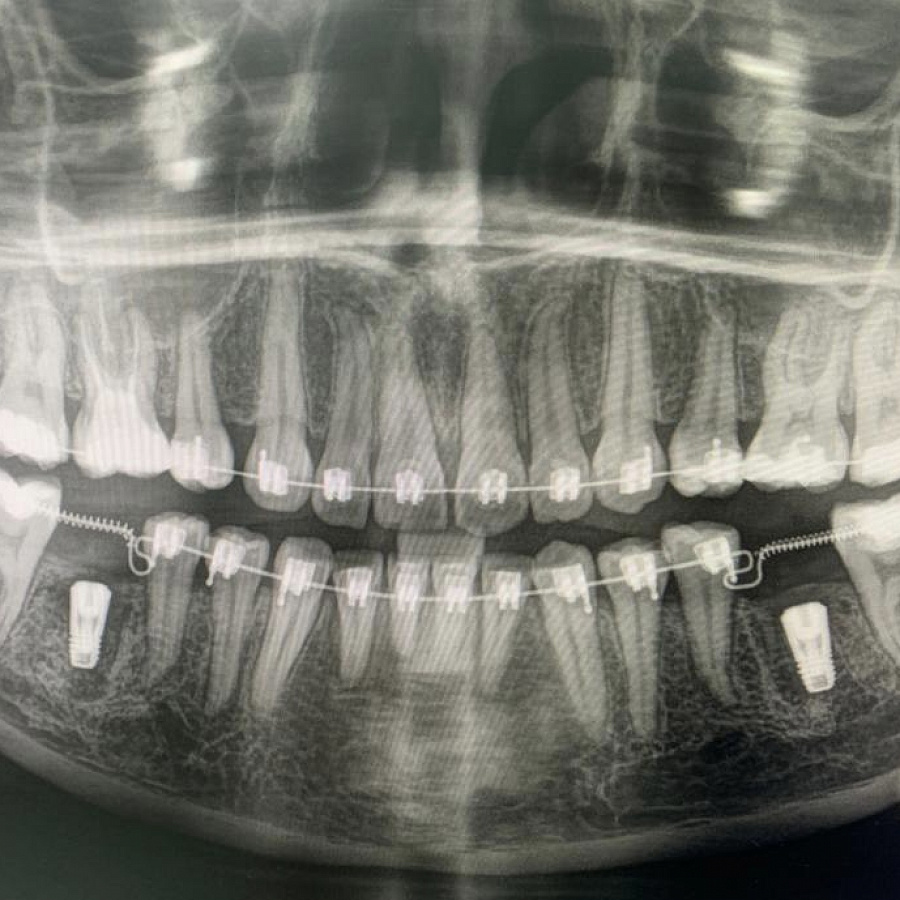

Пациентка начала ортодонтическое лечение и за 5 месяцев до окончания лечения ей удалили нижние шестерки и поставили импланты. За месяц до конца лечения установили формирователи десны. На момент снятия брекетов были сняты слепки под постоянные коронки на имплантатах.

В этом случае одновременно пациент закончил ортодонтическое, хирургическое и ортопедическое лечение. Что возможно только при одновременном подходе команды врачей.

Результат лечения